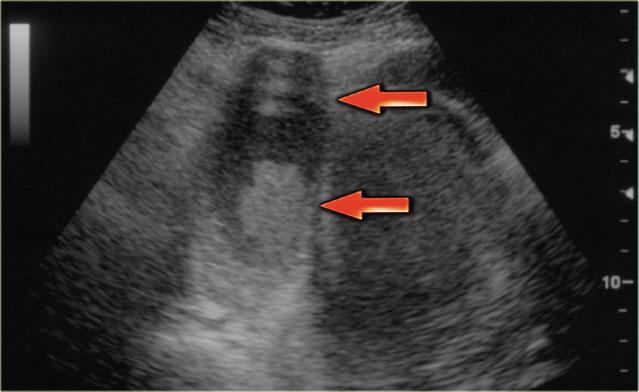

Các hình ảnh siêu âm cho thấy nhiều tổn thương buồng trứng phải đơn giản và một tổn thương phức tạp (mũi tên đỏ).

Tổn thương sau biểu hiện hồi âm mức thấp lan tỏa và không có tín hiệu dòng chảy trên Doppler.

Lưu ý có xuyên âm tốt (mũi tên xanh).

Các đặc điểm này gợi ý sự hiện diện của nang xuất huyết.

Tiếp tục xem các hình ảnh MRI.